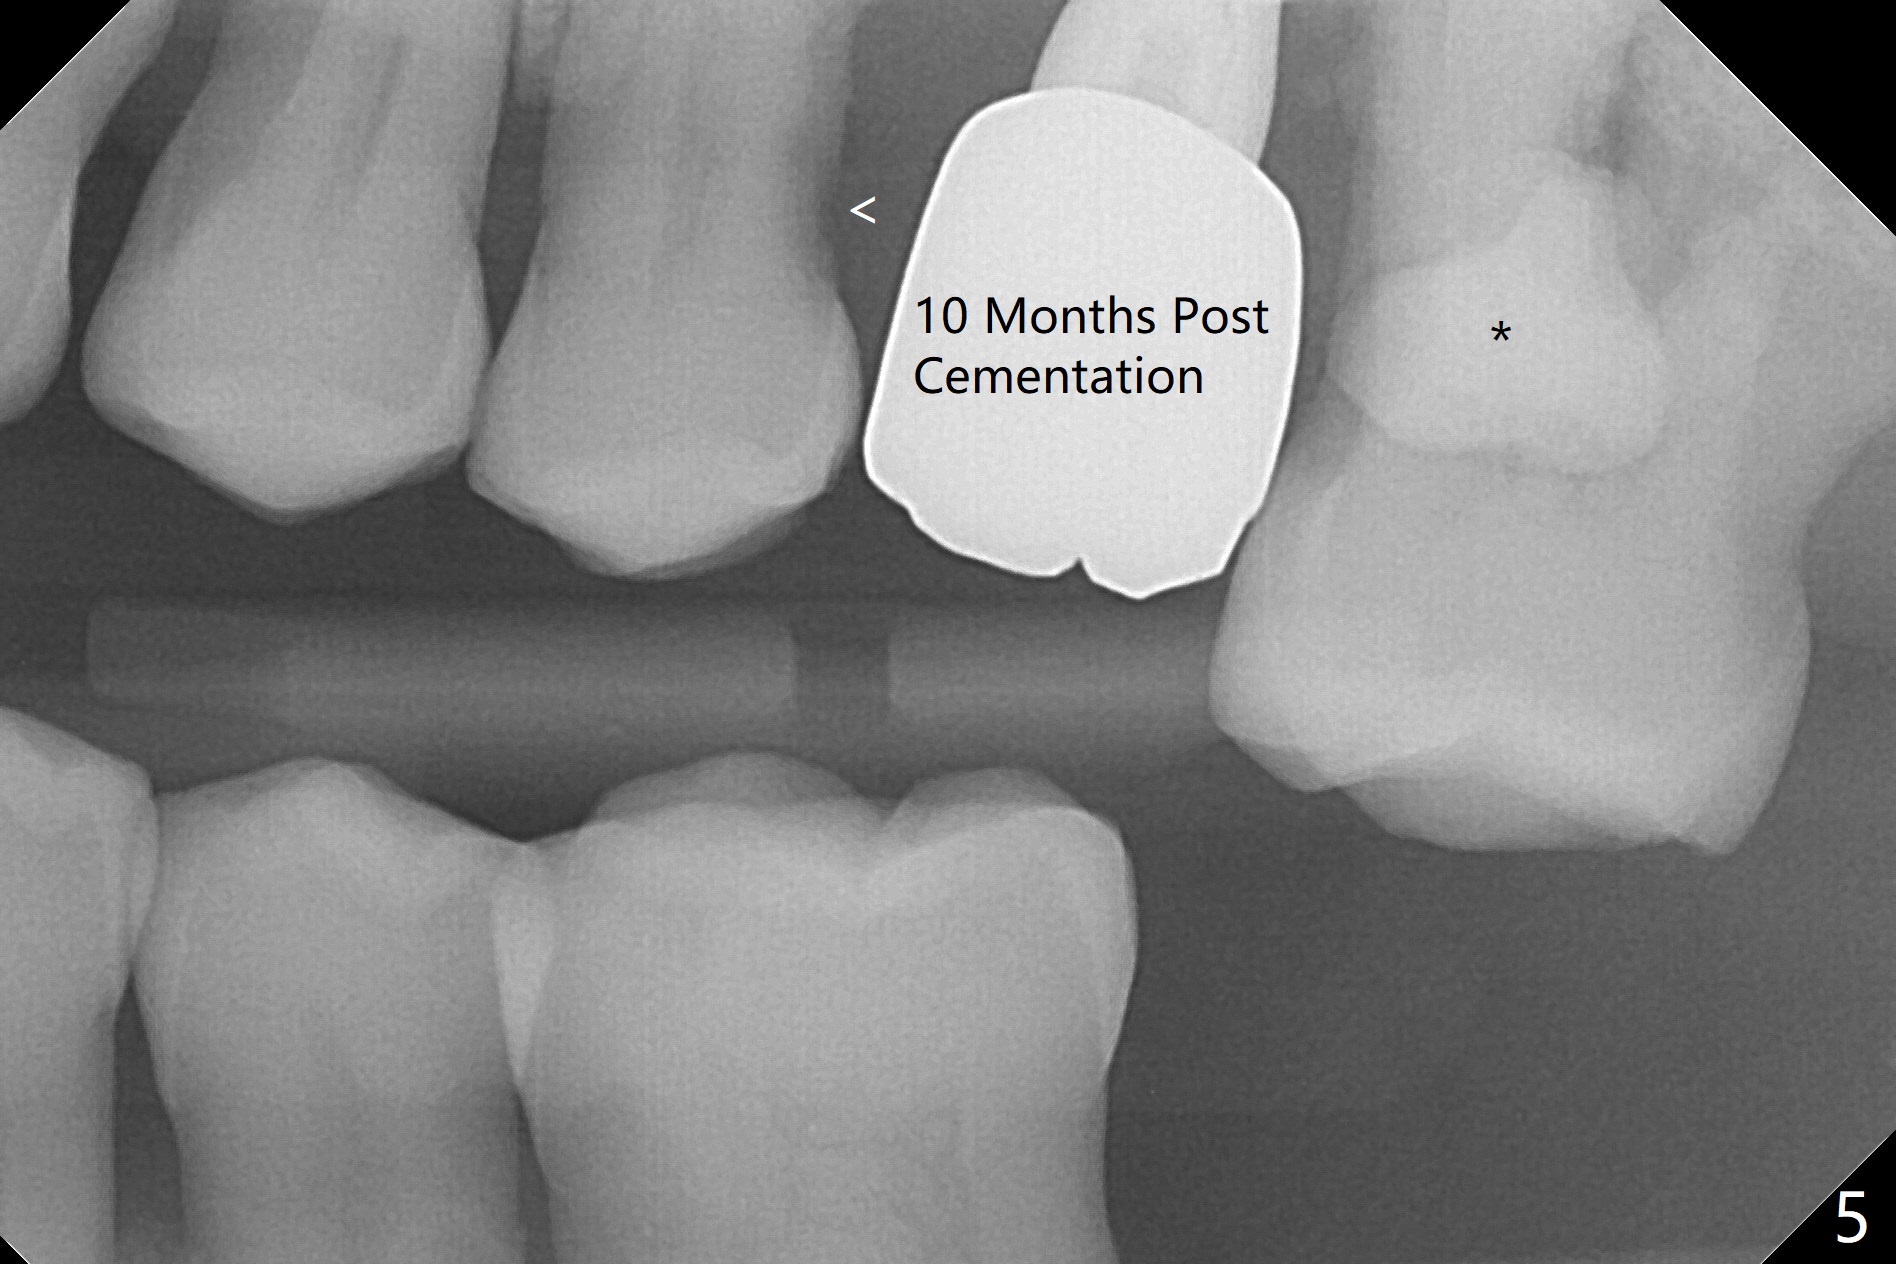

The patient is extremely nervous about implant placement at #14. Access is obtained with a 4 mm tissue punch, which appears to be the least traumatic. Since the gingiva is ~ 5 mm thick, vision is poor and it is difficult to change osteotomy buccally. It seems a 6 mm tissue punch is more appropriate for this case. The initial osteotomy depth is 14 mm (Fig.1). Since the tooth #15 is nonsalvageable because of furca caries and bone loss (Fig.1 *), the distal osteotomy at #14 is apparently acceptable. When a 5x13 mm implant is placed with >50 Ncm (Fig.2), the implant is subcrestal clinically except palatal (osteotomy not buccal enough), which is consistent with bitewing view (Fig.3). A 5.5x5 mm healing abutment is placed. Surprisingly the fearful patient does not experience any pain. Tissue punch is an atraumtic measure. A larger one (6 mm) allows more room to change osteotomy. The access can be closed with larger healing abutment. If this implant fails due to periimplantitis, it is due to palatal placement with too large the implant (5 mm vs. 4 mm at #3). Palpate the bone prior to changing next large drill when performing a flapless procedure. The implant seems to be osteointegrated 5 months postop; the furca caries (Fig.4 *) is taken care of before impression with a 4.5x5(4) mm abutment. Distal caries of the tooth #13 is found 10 months post cementation (Fig.5). Strict oral hygiene for prevention should have been given after composite for the furca of the tooth #15 (*).